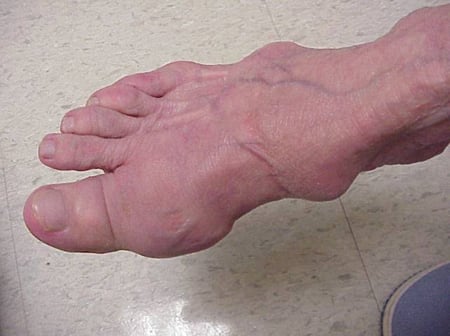

Gout flares can occur in joints that look normal, or in joints that have easily visible deposits of uric acid. These deposits are called tophi (See Figures: 7a and 7b: Tophi on Foot and Over Achilles' Tendon, Figure 8: Tophus on Elbow, Figure 9: Tophi on Hands, and Figure 10: Large Tophus of Finger) and can be in numerous locations, but especially on the feet and elbows. In Figure 9, the little finger of the right hand is bandaged since fluid was just removed from it, which demonstrated innumerable uric acid crystals.

Photo showing tophi on a foot

Figure 7a: Tophi on Foot